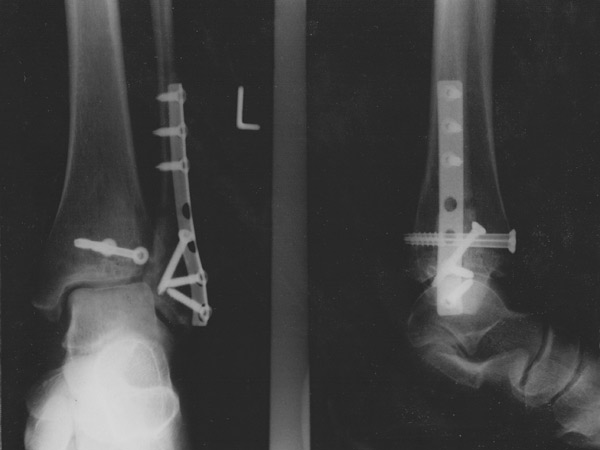

Das vierte Loch von oben ist nun leer...